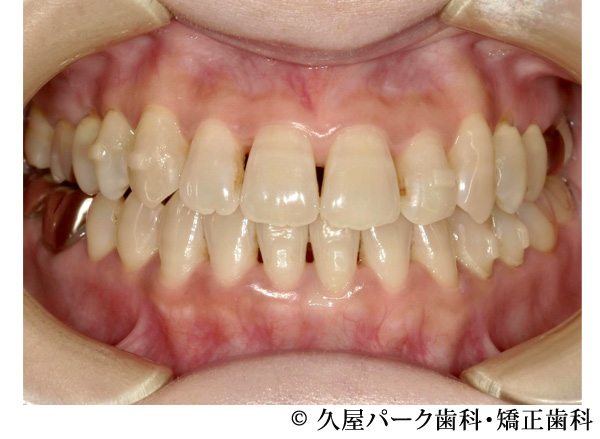

【症例3】叢生(歯のでこぼこ)の症例

- 治療前

- 治療後

- 治療名

- 叢生(歯のでこぼこ)の症例

- 費用

- 660,000円(税込)

※矯正相談・精密検査・オーダーメイド治療計画の費用はいただいておりません - 期間

- 2年4ヵ月

- 通院

- 1ヵ月ごと

- 性別・年代

- 女性・20代

治療内容

患者様の症状

全体的にでこぼこが気になるということで当院で治療を開始された患者様です。

治療法

ワイヤー矯正での歯並び改善

上下左右4番抜歯 -

治療結果

でこぼこが改善されました。

※治療結果は個人差があります。

治療を行う上での注意点(リスク・副作用)

・治療の初期段階では、痛みや不快感が生じやすくなりますが、一週間前後で慣れます

・歯の動き方には個人差があるため、予想された治療期間より延長する場合があります